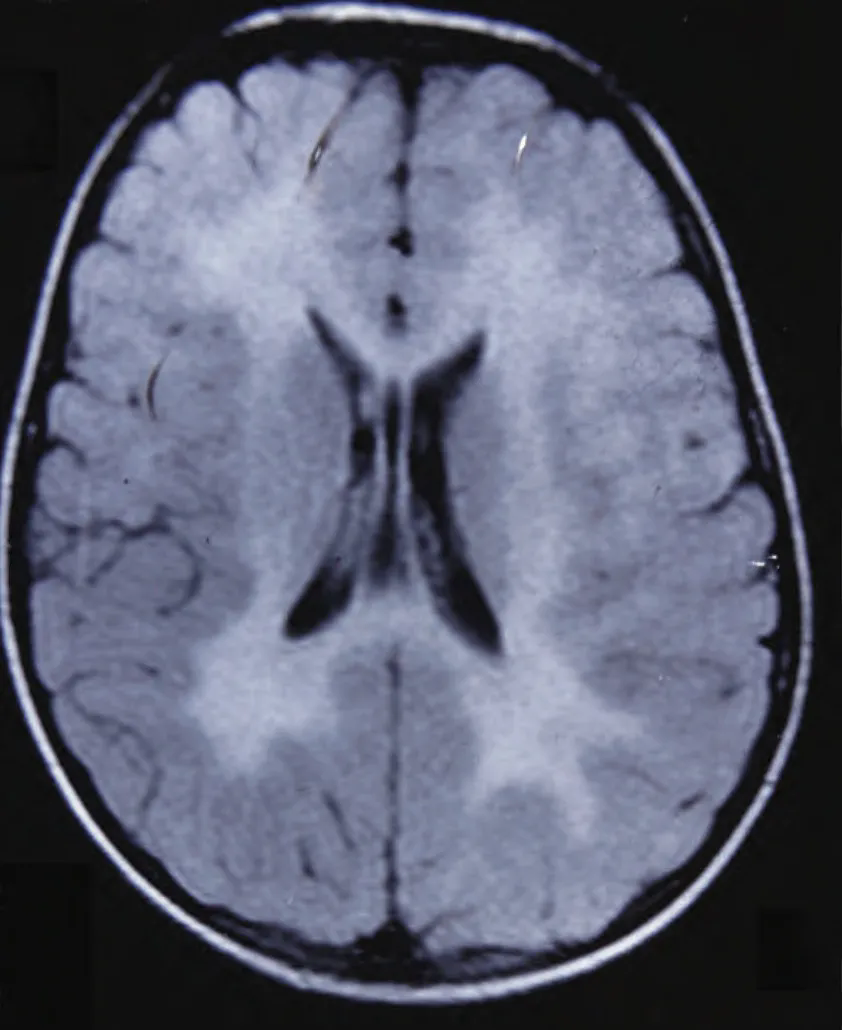

15、脑白质病变是一个非常宽泛的概念,有的脑白质病变会严重影响寿命,有的则没有多大影响,具体如下1目前最常见的脑白质病变指的是缺血性脑白质病,在磁共振的影像学检查上,可以在FLAIR相上看到多发性的高信号,大多数和脑动脉粥样硬化小动脉末梢缺血缺氧有关其本质上是白质纤维的脱髓鞘病变。

2、1 缺血性脑白质病变 对寿命影响不大这种病变在60岁以上的老年人群中较为常见,主要由脑动脉粥样硬化和小动脉末梢缺血缺氧引起它本质上是白质纤维的脱髓鞘病变,通常不影响预期寿命 可能影响认知功能如果病变较多范围较广,可能会引起记忆力减退和认知功能障碍,但并不会直接导致寿命缩短2。